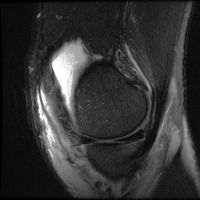

meniscal Computer Vision Project

Medical Diagnostics: Radiologists, orthopedic surgeons, and other medical professionals can utilize the "meniscal" model to accurately identify and classify meniscal lesions in knee MRI scans, thus improving the diagnosis and treatment process for patients with knee-related injuries and conditions.

Sports Injury Prevention and Management: Sports rehabilitation centers and athletic trainers can employ the "meniscal" model for analyzing knee scans of athletes to assess the health of their knees, track any changes over time, and tailor training regimens or treatments to prevent or recover from meniscal injuries.

Pre- and Post-Surgery Evaluation: Surgeons can use the "meniscal" model to analyze the knee scans taken before and after meniscal surgeries to evaluate the efficacy of the surgical intervention and make informed decisions about the patient's further treatment plan and rehabilitation process.